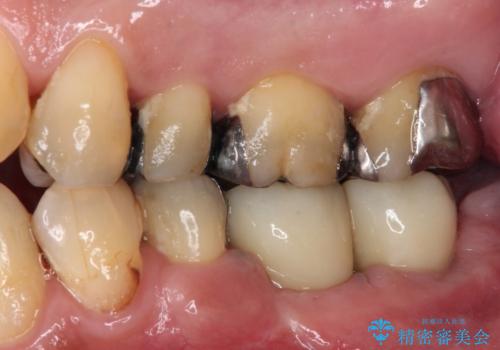

- 抜歯をしたものの、インプラントにするか入れ歯にするか悩んでいるうちに2年以上経過してしまったとのことで来院された患者様です。

自分の歯のように噛めるようにしたいとのことで、インプラントによる欠損補綴治療を行うこととしました。

インプラントにはストローマン社のSLActiveを使用し、埋入から補綴までおよそ3か月と、短期間で治療を進めることができました。